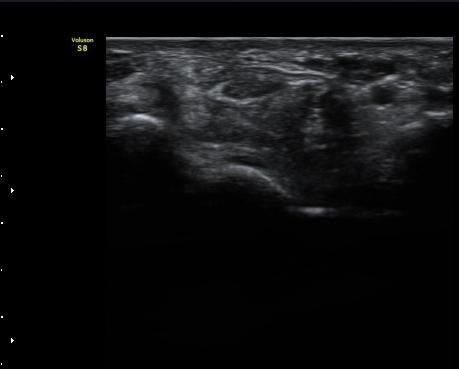

¼ö±Ù°ü¸»´Ü(trapezium ±âÁØ) Á¤Á߽Űæ Ⱦ´Ü¸é°Ë»ç¿¡¼­ Á¤Á߽ŰæÀÇ Àú¿¡ÄÚ ºÎÁ¾ÀÌ °üÂûµÈ´Ù(±×¸² 3)

ÀÌ´Â Åë»óÀûÀÎ ¼ö±Ù°üÁõÈıº¿¡¼­ º¸ÀÌ´Â ¾ç»ó°ú ´Ù¸¥ ¸ð½ÀÀÌ´Ù.